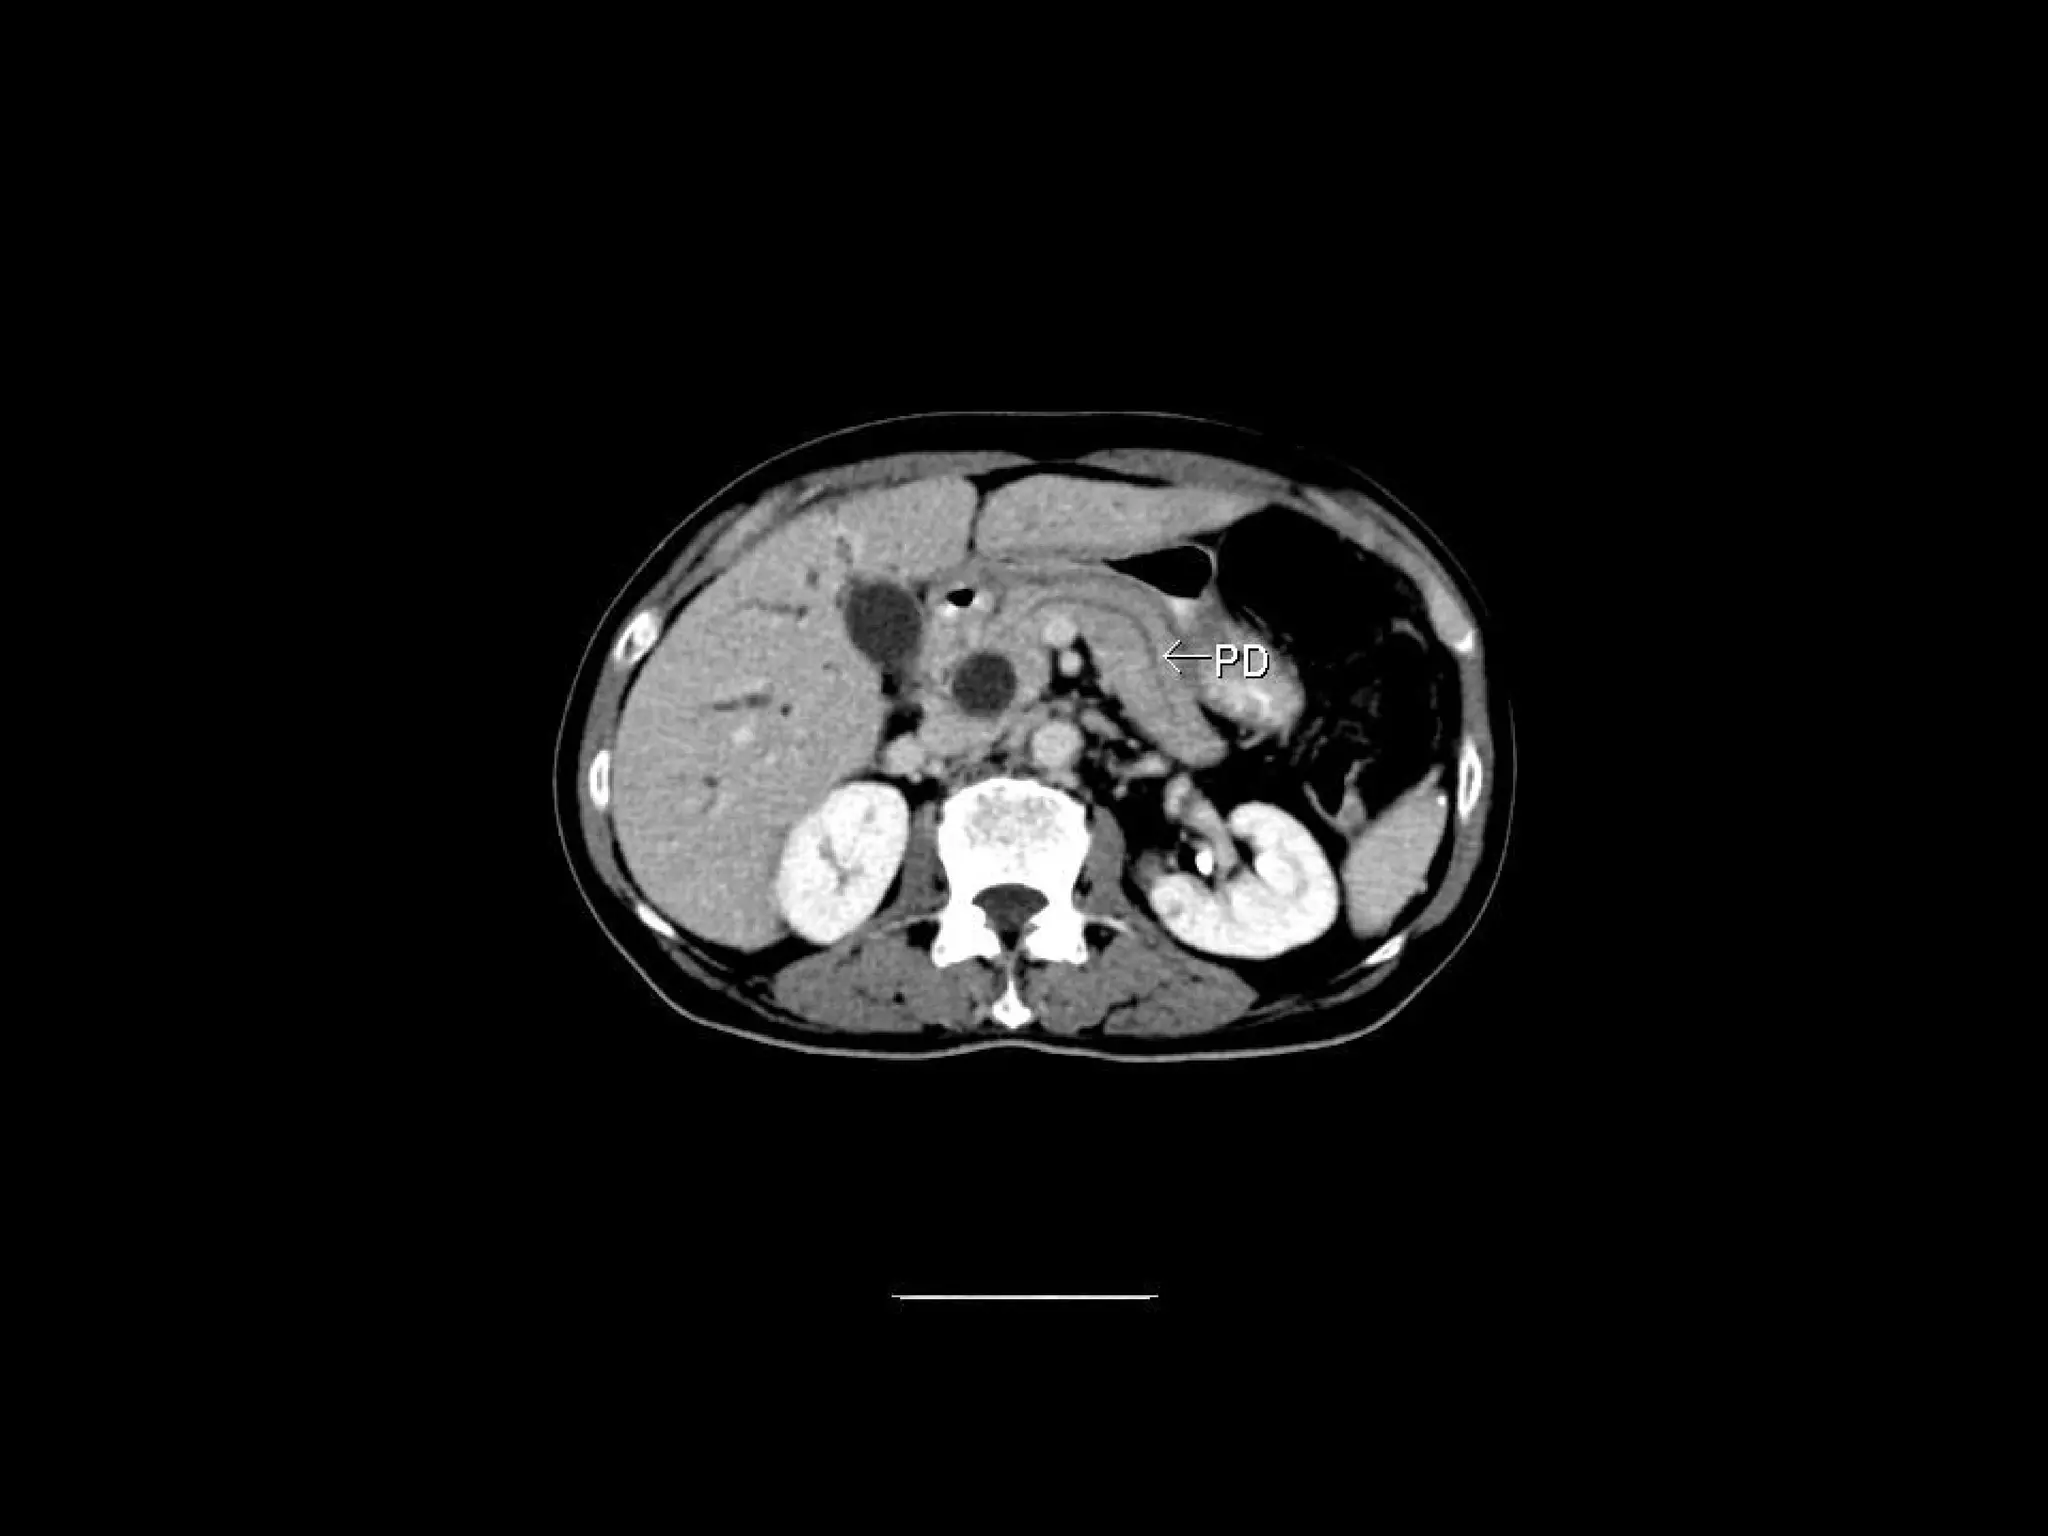

Radiographers are medical professionals who perform diagnostic imaging examinations and procedures to help physicians diagnose and treat diseases. They work under the supervision of radiologists to operate X-ray, CT, MRI, ultrasound and other medical imaging equipment and must have a strong understanding of human anatomy and pathology. Radiographers are responsible for correctly positioning patients, ensuring proper imaging techniques are used, and evaluating the quality of the resulting images.